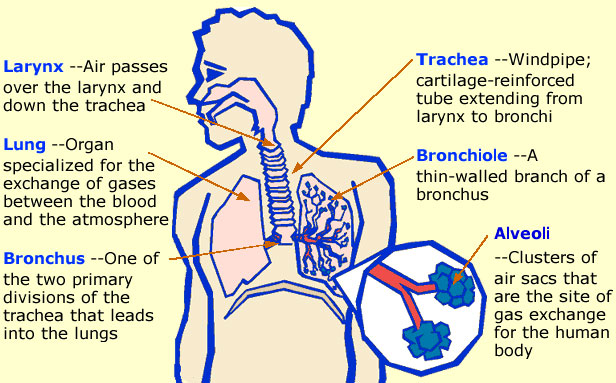

TOPIC: THE RESPIRATORY SYSTEM (HUMAN)

Respiration is the process by which food substances are broken down in our body to release the energy we need.

The body does not depend on food alone for the production of all the energy required. There is the need for oxygen, which we get from the air we breathe in to break down food substances in our body releasing energy and some waste products.

PARTS OF THE HUMAN RESPIRATORY SYSTEM

The human respiratory system consists of a number of organs which work together to ensure the supply of oxygen to the body cells and the removal of carbon (IV) oxide from the cells.

These organs are:

(1 ) nostrils (2) larynx (3) pharynx (4) trachea (wind pipe) (5) bronchi (6) lungs (7 ) bronchioles (8) alveoli (9) mouth

(1) Nostrils:

Air enters the body through the nostrils which are lined with a membrane of cells that secrets mucus which moistens the air we breathe.

(2) Pharynx:

The nostrils lead into the pharynx which is the lower end of the mouth cavity.

(3) Larynx:

The pharynx leads into the larynx which is also called the voice box. The larynx leads into the trachea, which is also called the wind pipe.

(4) Bronchi:

The trachea leads into the bronchi, each bronchus leads into a lung.

(5) Lungs: each bronchus leads into a lung. Inside the lungs are tiny tubes called bronchioles. The bronchioles branch again into alveoli.

2. Cellular Respiration:

This is the process by which oxygen breathed in from the atmosphere is used in the breaking down of food substances in our body cells to release needed energy with CO2 and H2O as the waste products.